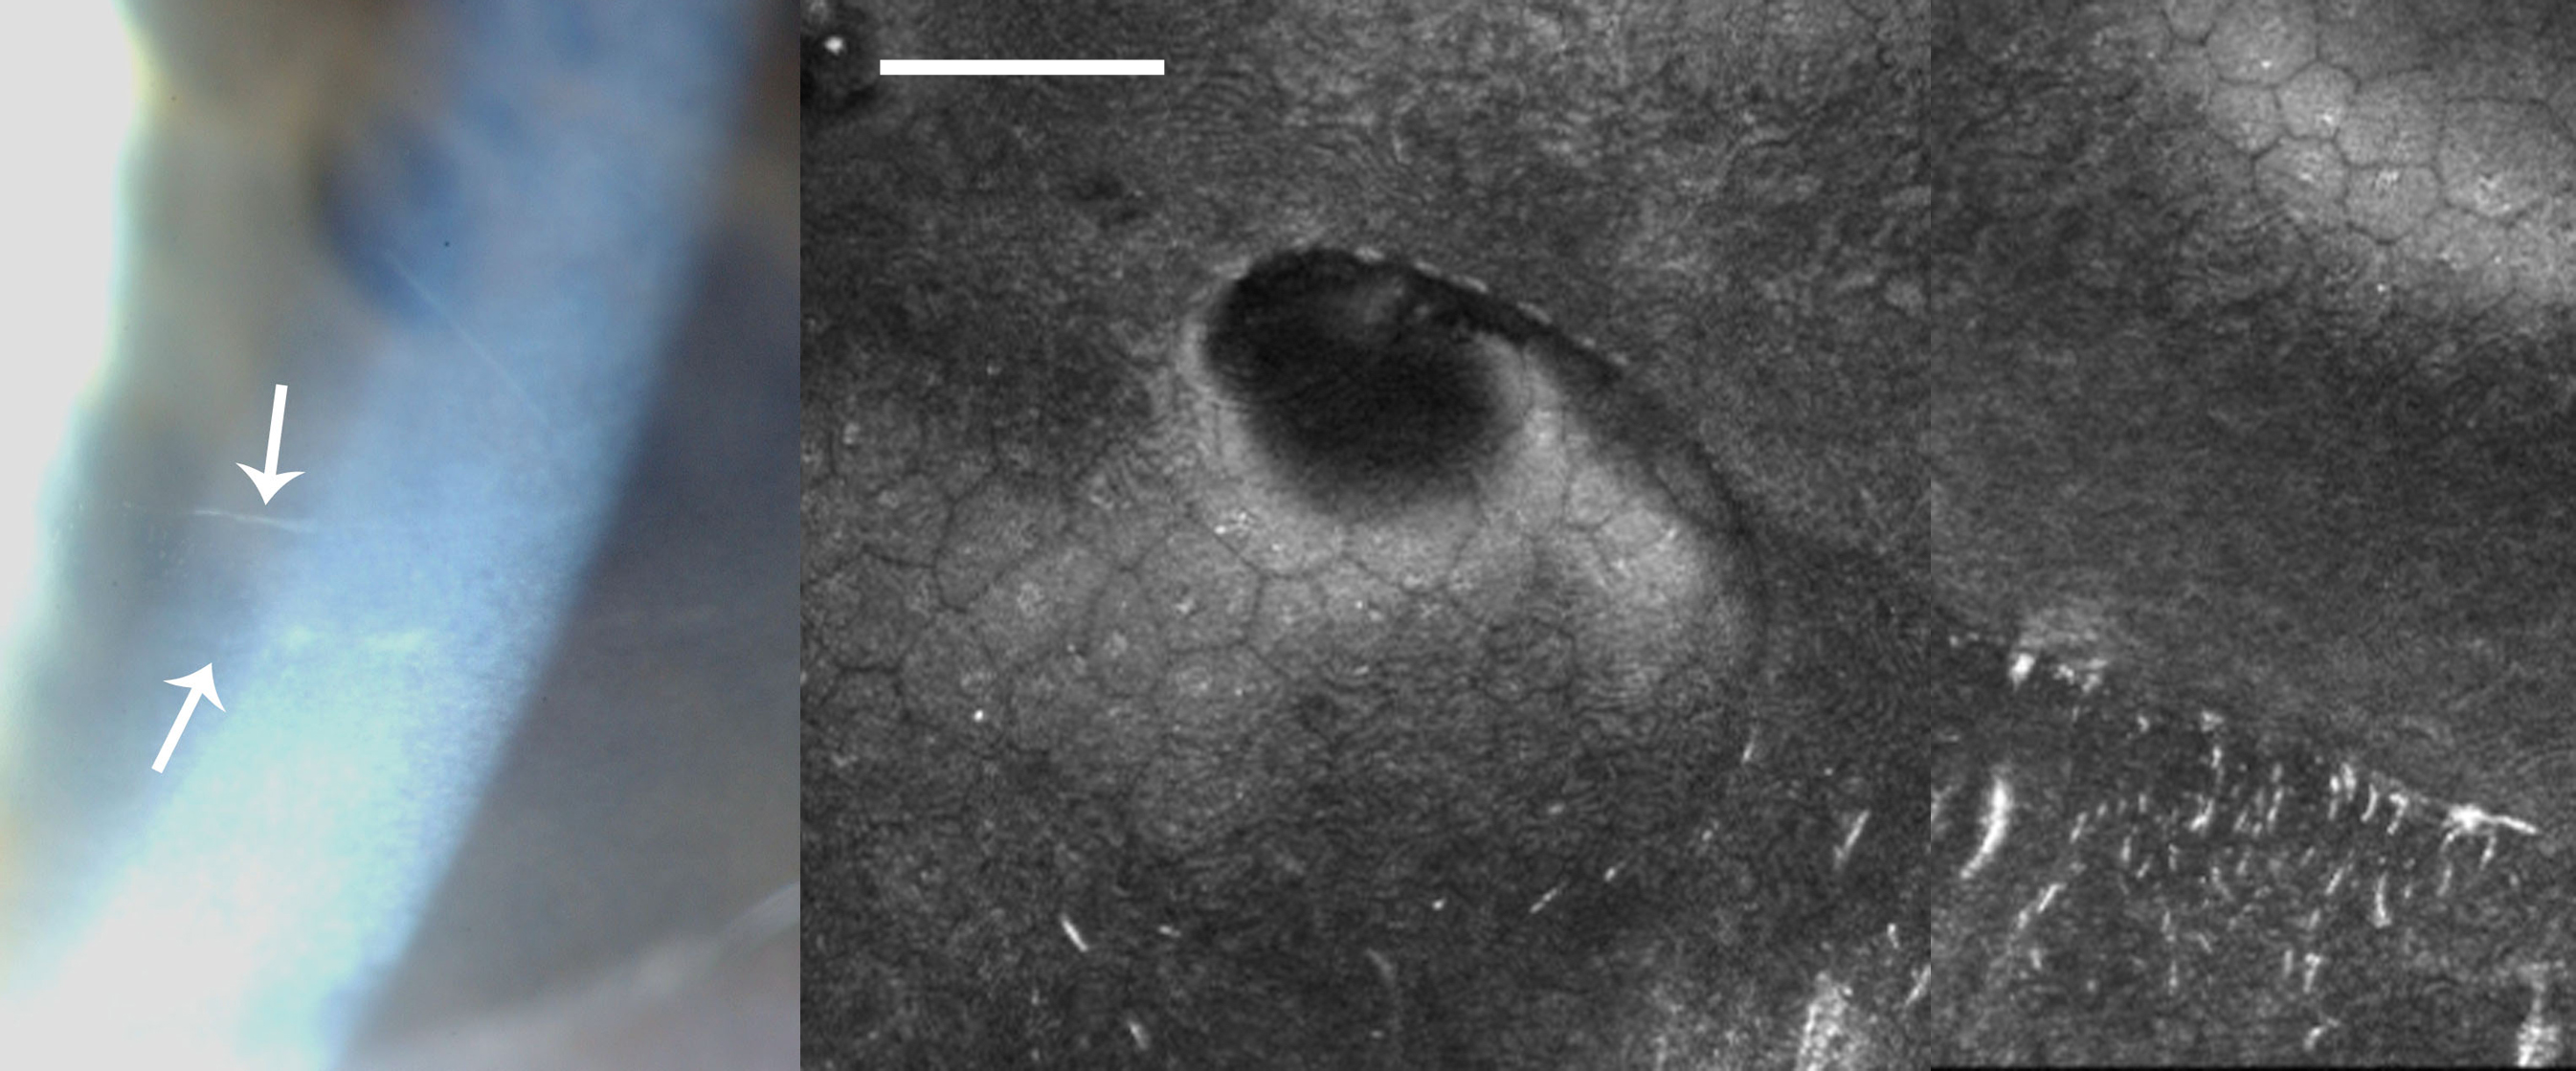

Figure 3. Clinical images of Case 1. A: A slit-lamp photograph of Case 1 showing a posterior polymorphous dystrophy band lesion (arrows). B: In vivo confocal microscopy in this patient shows undulation of Descemet’s membrane and the endothelial surface, with needle-shaped

hyper-reflectivity at the level of Descemet’s membrane. (Scale bar=100 μm)